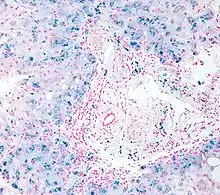

Micrograph of liver biopsy showing iron deposits due to haemosiderosis. Iron stain.

Histopathology of the liver, showing Kupffer cells with significant hemosiderin deposition (shown next to a hepatocyte with lipofuscin pigment, which is a common normal finding). H&E stain.

Prussian blue iron staining, highlighting the hemosiderin pigment as blue. This finding indicates mesenchymal iron overload (within Kupffer cells and/or portal macrophages) rather than parenchymal iron overload (within hepatocytes).[40]

Liver biopsy is the removal of small sample in order to be studied and can determine the cause of inflammation or cirrhosis. In someone with negative HFE gene testing, elevated iron status for no other obvious reason, and family history of liver disease, additional evaluation of liver iron concentration is indicated. In this case, diagnosis of hemochromatosis is based on biochemical analysis and histologic examination of a liver biopsy. Assessment of the hepatic iron index (HII) is considered the "gold standard" for diagnosis of hemochromatosis.